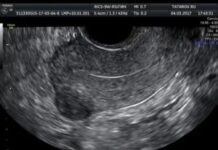

Ультразвуковая анатомия органов малого таза у женщин

Ультразвуковое исследование малого таза является безопасным и высокоточным методом обследования органов, которые расположены между тазовыми костями. Исследование данного типа позволяет увидеть органы в динамике,...